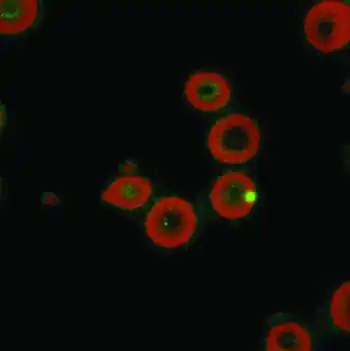

In mammals, each Bartonella species is highly adapted to its reservoir host as the result of intracellular parasitism and can persist in the bloodstream of the host. Intraerythrocytic parasitism is only observed in the acute phase of Carrion's disease. Bartonella species also have a tropism for endothelial cells, observed in the chronic phase of Carrion's disease and bacillary angiomatosis. Pathological response can vary with the immune status of the host. Infection with B. henselae can result in a focal suppurative reaction (CSD in immunocompetent patients), a multifocal angioproliferative response (bacillary angiomatosis in immunocompromised patients), endocarditis, or meningitis.[3][2][36][37]